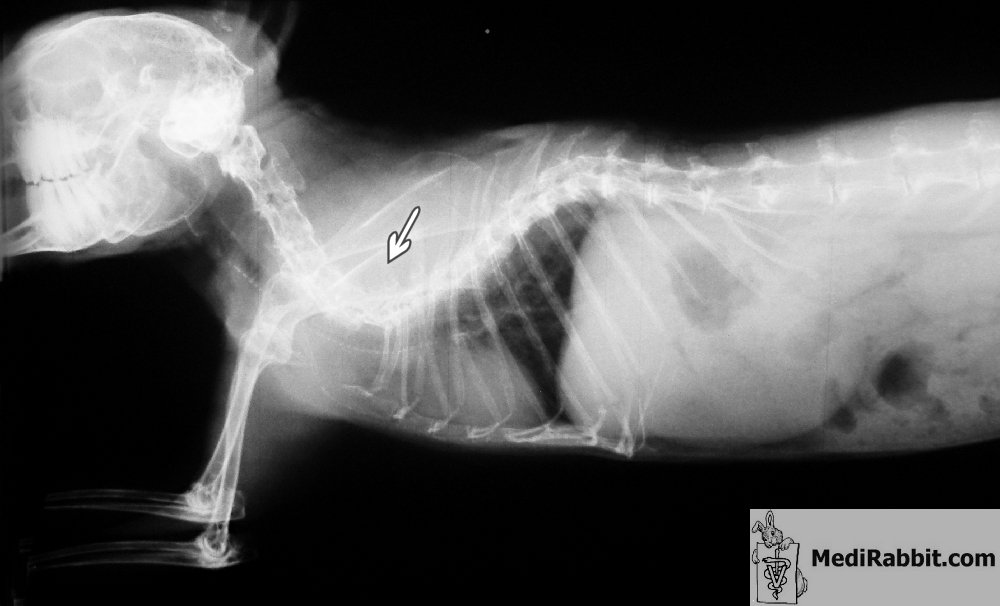

Les radiographies de

Pépin, vues latérales et dorso-ventrales, montrent la déformation sévère de la

colonne vertébrale. Un lapin avec une telle anomalie développe souvent une parésie

des membres inférieurs qui progresse avec le temps. La dégénérescence des

disques vertébraux (spondylarthropathie) contribue

à la démarche difficile. Le lapin aura de la peine à soigner son pelage et à récupérer

les caecotropes.

Dr Maassen, cabinet Grodisiabois, Liège (Belgique) Lapin

souffrant de lordose thoracique, une courbure de la colonne vertébrale vers

l’intérieur du corps, accompagné de parésie des membres inférieurs.